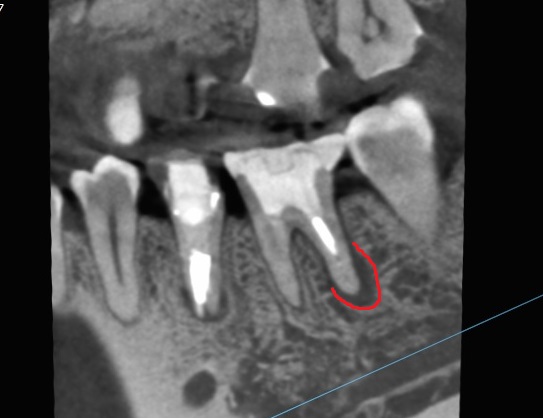

「歯を抜かないといけない」と言われたが、当院で抜かずに終えました。